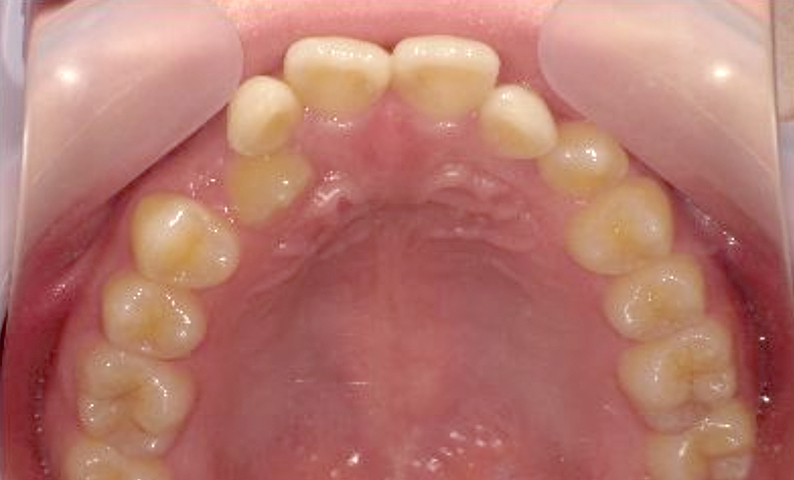

症例_025 上顎だけの部分矯正

治療期間:7ヶ月金額:30万円+税女性前歯のガタガタ上の前歯だけ

| Before | After |